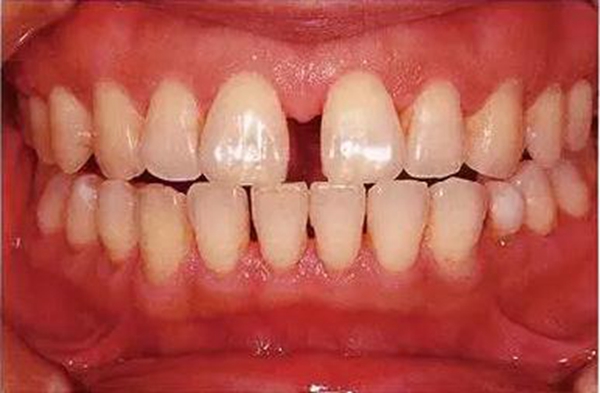

●參考病例① 35歲女性

35歲女性。妊娠4個月。過去雖然接受過刷牙指導,但菌斑控制狀態(tài)依然不理想?;颊哂邪l(fā)現(xiàn)自己刷牙時牙齦出血。

●參考病例② 25歲女性

25歲女性。菌斑控制狀態(tài)不好。齦溝除磨牙處外全在3mm以下,X光照片上左上、右下、左下的第一磨牙上有垂直性骨吸收。這個病例是參考病例①10年前的狀態(tài),是典型的侵襲性牙周炎局部型。